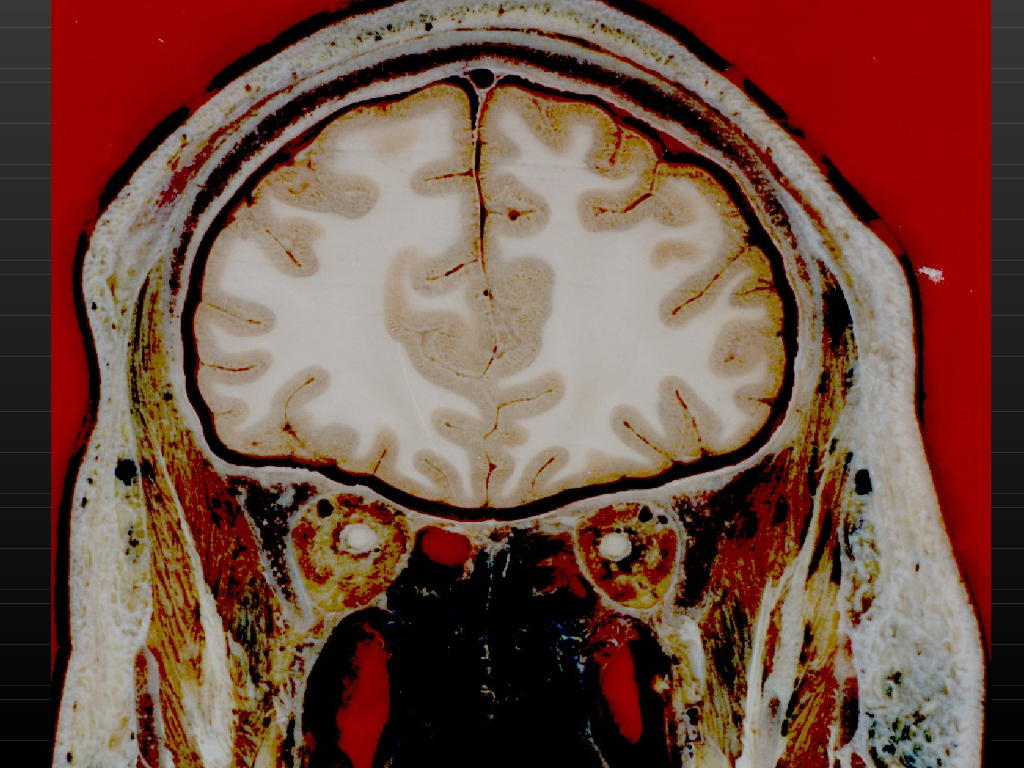

《断层影像解剖学》演示文稿-头部冠状断层解剖与MRI.pdf